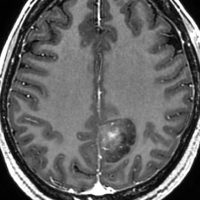

小児の神経節細胞腫 gangliocytoma グレード1(過誤腫のような良性腫瘍)

10才の時に,複雑部分発作(症候性てんかん)で発症しました。吐き気を感じた後に嘔吐して意識が遠くなる(意識減損)という症状であり,側頭葉てんかんです。脳波では左側頭葉に徐波律動がみられました。発作は頻回でしたがカルバマゼピンの投与で抑制されていましたが,MRIで腫瘍が発見されました。

左内側側頭葉グリオーマ mesial temporal glioma と呼ばれる腫瘍です。左の扁桃体,海馬鉤,海馬,海馬傍回に腫瘍が浸潤しています。T2強調画像とFLAIRでまだらな高信号で境界ははっきりしません。mass effectが少なく,増殖増大傾向のある腫瘍には見えないのが特徴です。下段右のように部分的にガドリニウム増強されるのも神経節細胞腫の特徴かもしれません。しかし,神経節膠腫,乏突起膠腫,乏突起星細胞腫(グレード2)なども疑われます。

手術中の脳波モニターでは,棘波が上側頭回の後方(ウェルニッケ領域)に存在し,深部電極刺入で海馬近傍にも棘波がみられましたが,もちろん上側頭回や海馬の切除はしませんでした。扁桃体 amygdala と海馬鈎 uncus の腫瘍部分のみを切除して手術を終了しています。海馬と海馬傍回には腫瘍を残しました。上のMRIは,その後6年経過した後のものですが腫瘍は全く同じ大きさです。抗てんかん薬も止めて,発作は全く生じていません。このような腫瘍は,扁桃体と海馬鉤を摘出することで,発作を完全に止めることができることがあります。ですから,最初の手術では,リスクのある余分な脳切除をしません。

大脳皮質に大型の核を有する円形の神経細胞が散在しています。神経細胞間にグリア細胞がありますが腫瘍性増殖を示しません。MIB-1は1%以下でした。血管周囲にリンパ球浸潤があります。